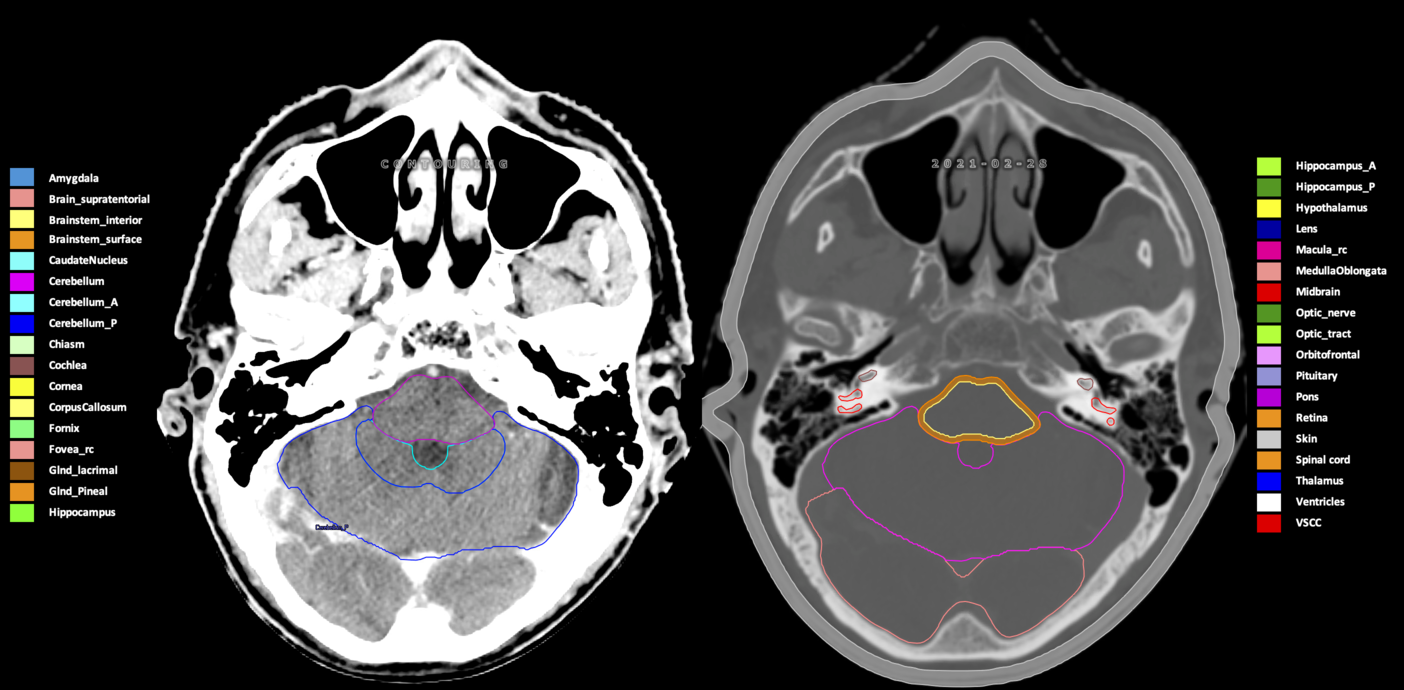

Included are all OARs known to be relevant for radiation-induced toxicity in neuro-oncology: brain, brainstem (midbrain, pons, medulla oblongata), chiasm, cerebellum (anterior & posterior), cochlea, cornea, hippocampus (anterior & posterior), hypothalamus, lens, lacrimal gland, optic nerve, pituitary, skin, and vestibular & semicircular canals. To further facilitate research on cognition, vision and radiological changes after irradiation of the brain, potential clinically-relevant OARs are included: amygdala, caudate nucleus, cerebellum (anterior & posterior), corpus callosum, fornix, macula, optic tract, orbitofrontal cortex, periventricular space (PVS), pineal gland, and thalamus.

Three-dimensional delineation of the 25 consensus OARs for neuro-oncology are shown on CT (WW/WL 120/40, 3000/600), 3T MR images, (T1Gd, T2FLAIR 1mm) and 7T MR (MP2RAGE 0.7 mm). All are presented in transversal, sagittal and coronal view.